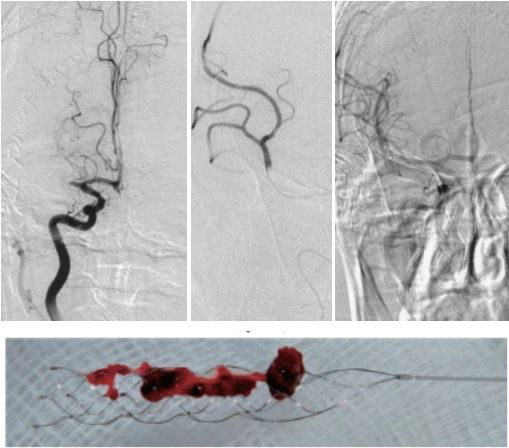

我們?nèi)粘K哪X梗死雖然指的是腦組織的壞死,但病因在腦血管,腦血管就如同一棵根深葉茂的大樹,如果是小樹枝凋零,無傷大局,如果是主干出了問題,就無法再煥發(fā)生機(jī)。顱內(nèi)大血管就如同大樹的主干,如果大塊的血栓堵在顱內(nèi)大血管用常規(guī)的手段無法清除,則后果不堪設(shè)想,這種情況應(yīng)盡快取出血栓。支架取栓手術(shù)簡單快速,其基本原理類似心臟支架的放置過程。醫(yī)生僅需使用一根細(xì)穿刺針在局部麻醉下進(jìn)行簡單的下肢股動(dòng)脈的穿刺,即可建立一條通向顱內(nèi)的高速公路,將導(dǎo)管通過股動(dòng)脈放入顱內(nèi),輸送取栓裝置至血栓堵塞的血管,取栓裝置像一只伸向血栓的手,牢牢抓住血栓,將其整體取出,被堵塞的血管能夠迅速恢復(fù)血流,挽救瀕臨壞死的腦組織。

支架取栓是一種微創(chuàng)的手術(shù),僅需進(jìn)行股動(dòng)脈穿刺置入導(dǎo)管,將取栓支架置入顱內(nèi)病變處,患者幾乎無痛苦。

將腦梗患者快速轉(zhuǎn)運(yùn)至心導(dǎo)管室,清醒患者僅需局部麻醉,堵塞的血管可快速開通。

運(yùn)用取栓支架可以快速開通堵塞的血管,將血栓拉出體外,恢復(fù)腦組織正常血流。

患者突發(fā)肢體無力,意識不清,房顫病史,考慮急性腦梗塞。急診行全腦血管造影及支架取栓術(shù)。腦血管造影示右側(cè)大腦中動(dòng)脈閉塞,使用取栓支架將血栓拉出體外腦動(dòng)脈再通成功。